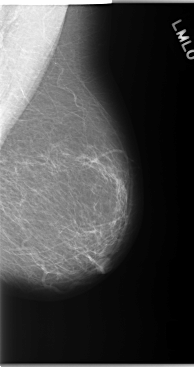

C_0143_1.RIGHT_MLO

C_0143_1.LEFT_MLO

C_0143_1.RIGHT_CC

C_0143_1.LEFT_CC

LEFT_MLO LINES 5872 PIXELS_PER_LINE 3096 BITS_PER_PIXEL 12 RESOLUTION 50 NON_OVERLAY